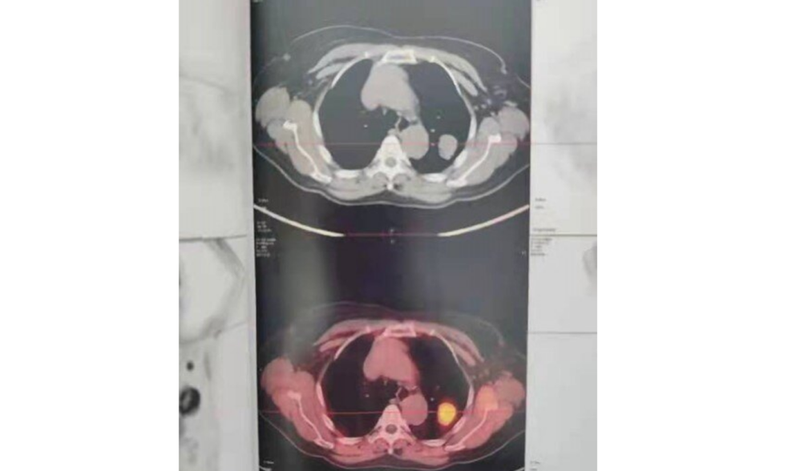

PET-CT显示病灶糖代谢摄取高,

诊断为恶性肿瘤